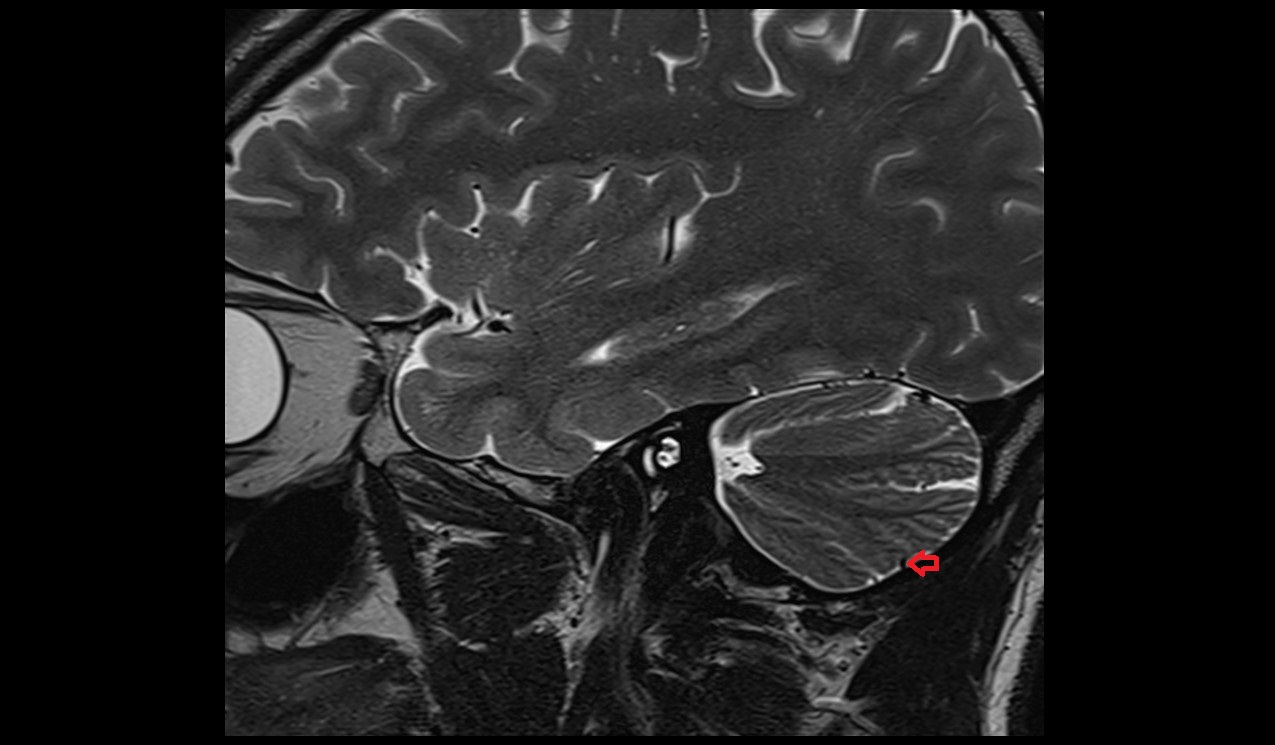

- Cerebellar tonsil (H IX)

- Crus I of ansiform lobule of cerebellum

- Crus II of ansiform lobule of cerebellum

- Paramedian lobule (HVII) of cerebellum

- Biventral lobule (HVIII) of cerebellum

- Lunogranicile fissure of cerebellum